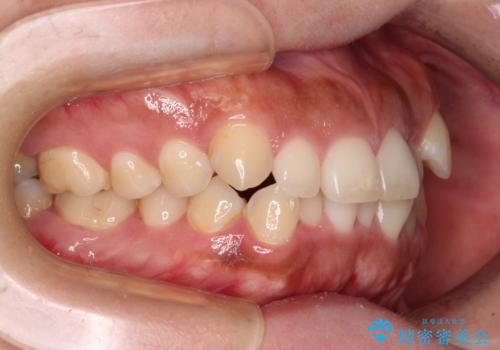

カリエールディスタライザーを併用したことで、すっきりとした口元になり、上下の正中を合わせることができました。

- 1年8ヶ月

- 10-30回